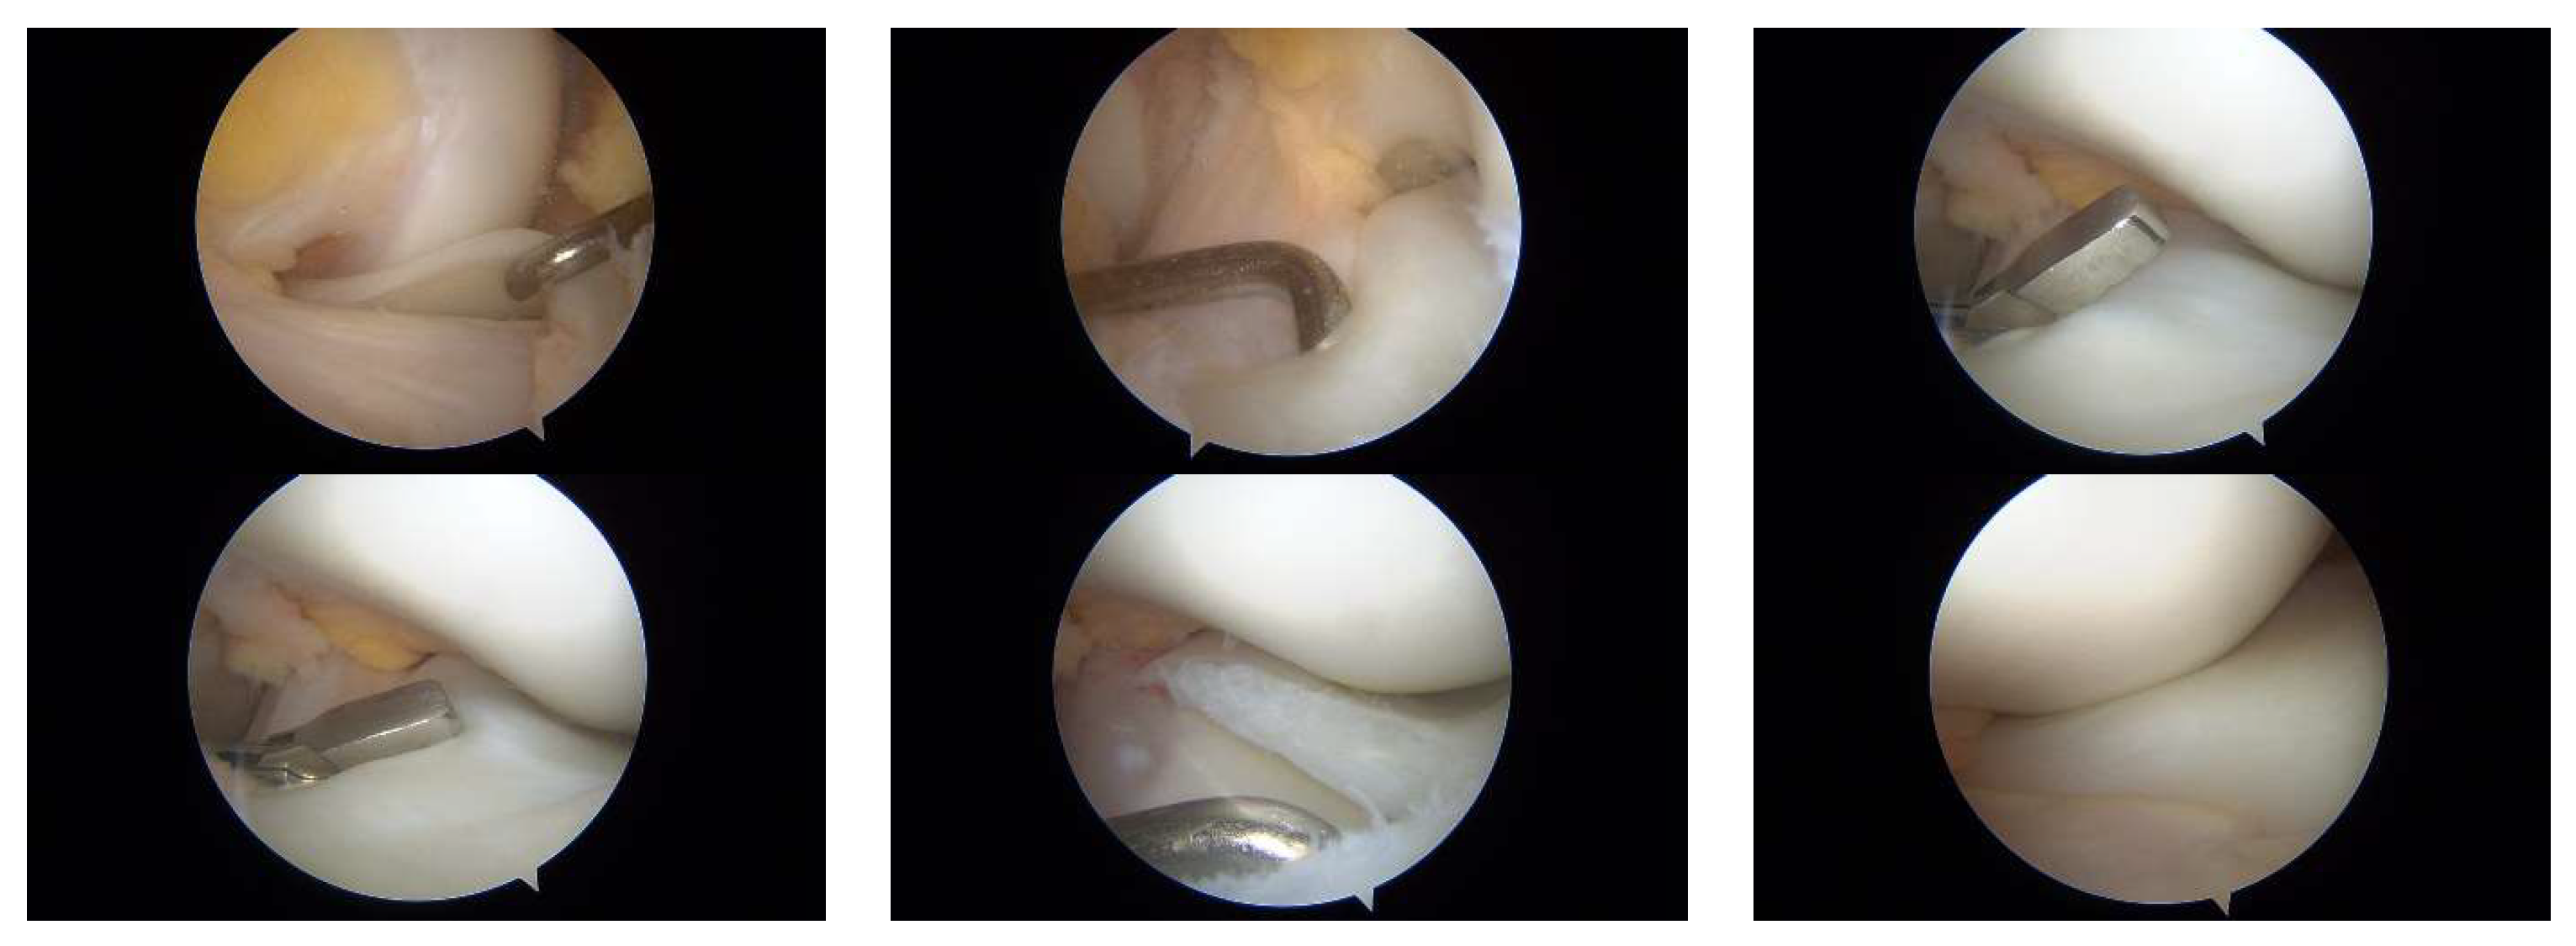

3.1. Case 1—P.E.

3.2. Case 2—S.C.S.

3.3. Case 3—G.L.